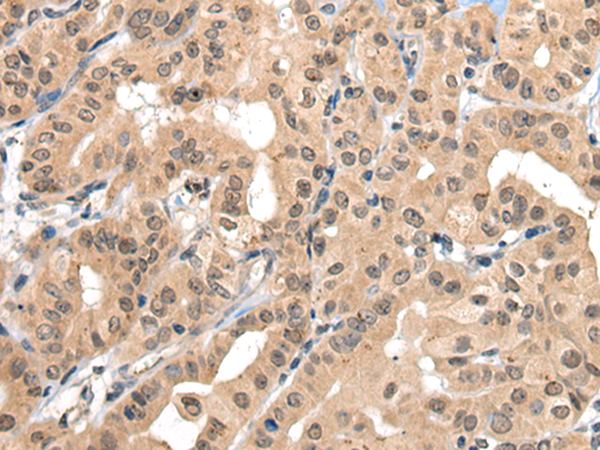

ELISA, IHC

IHC positive control:

Human thyroid cancer and human colorectal cancer

IHC Recommend dilution:

30-150